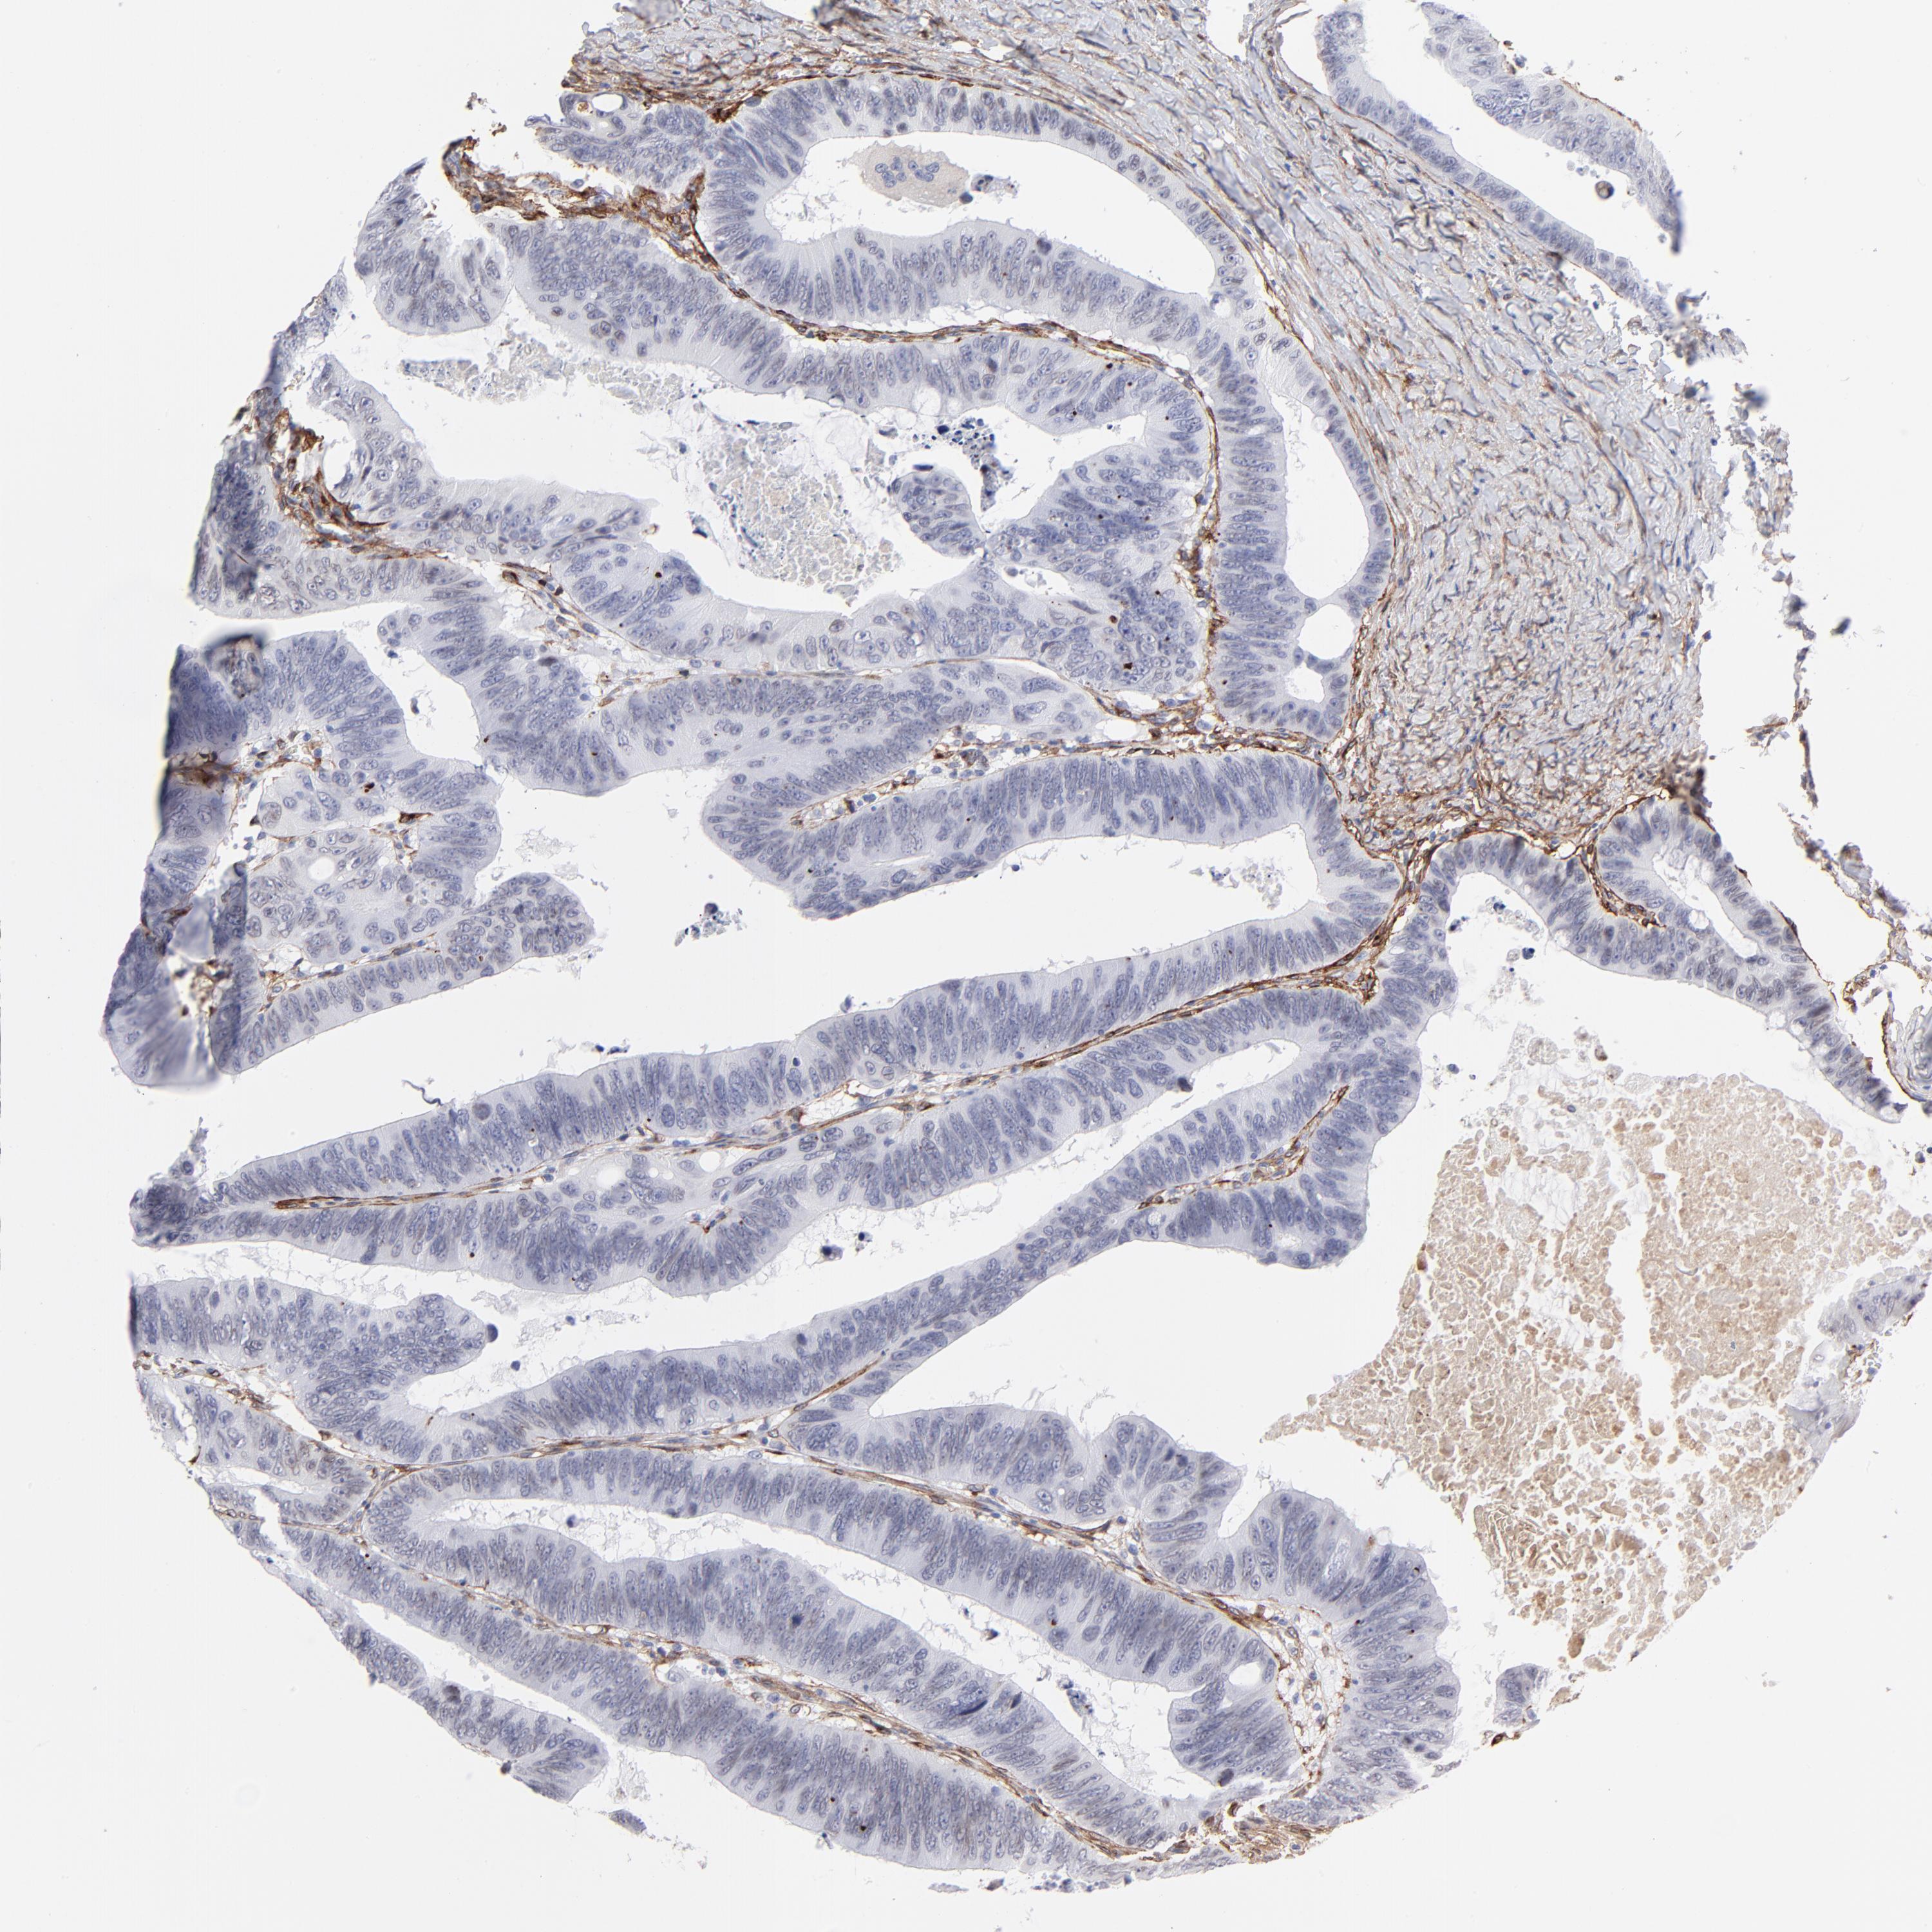

CANCER COLORECTAL CANCER Show tissue menu

Colorectal cancer

Human cancer

Colon adenocarcinoma